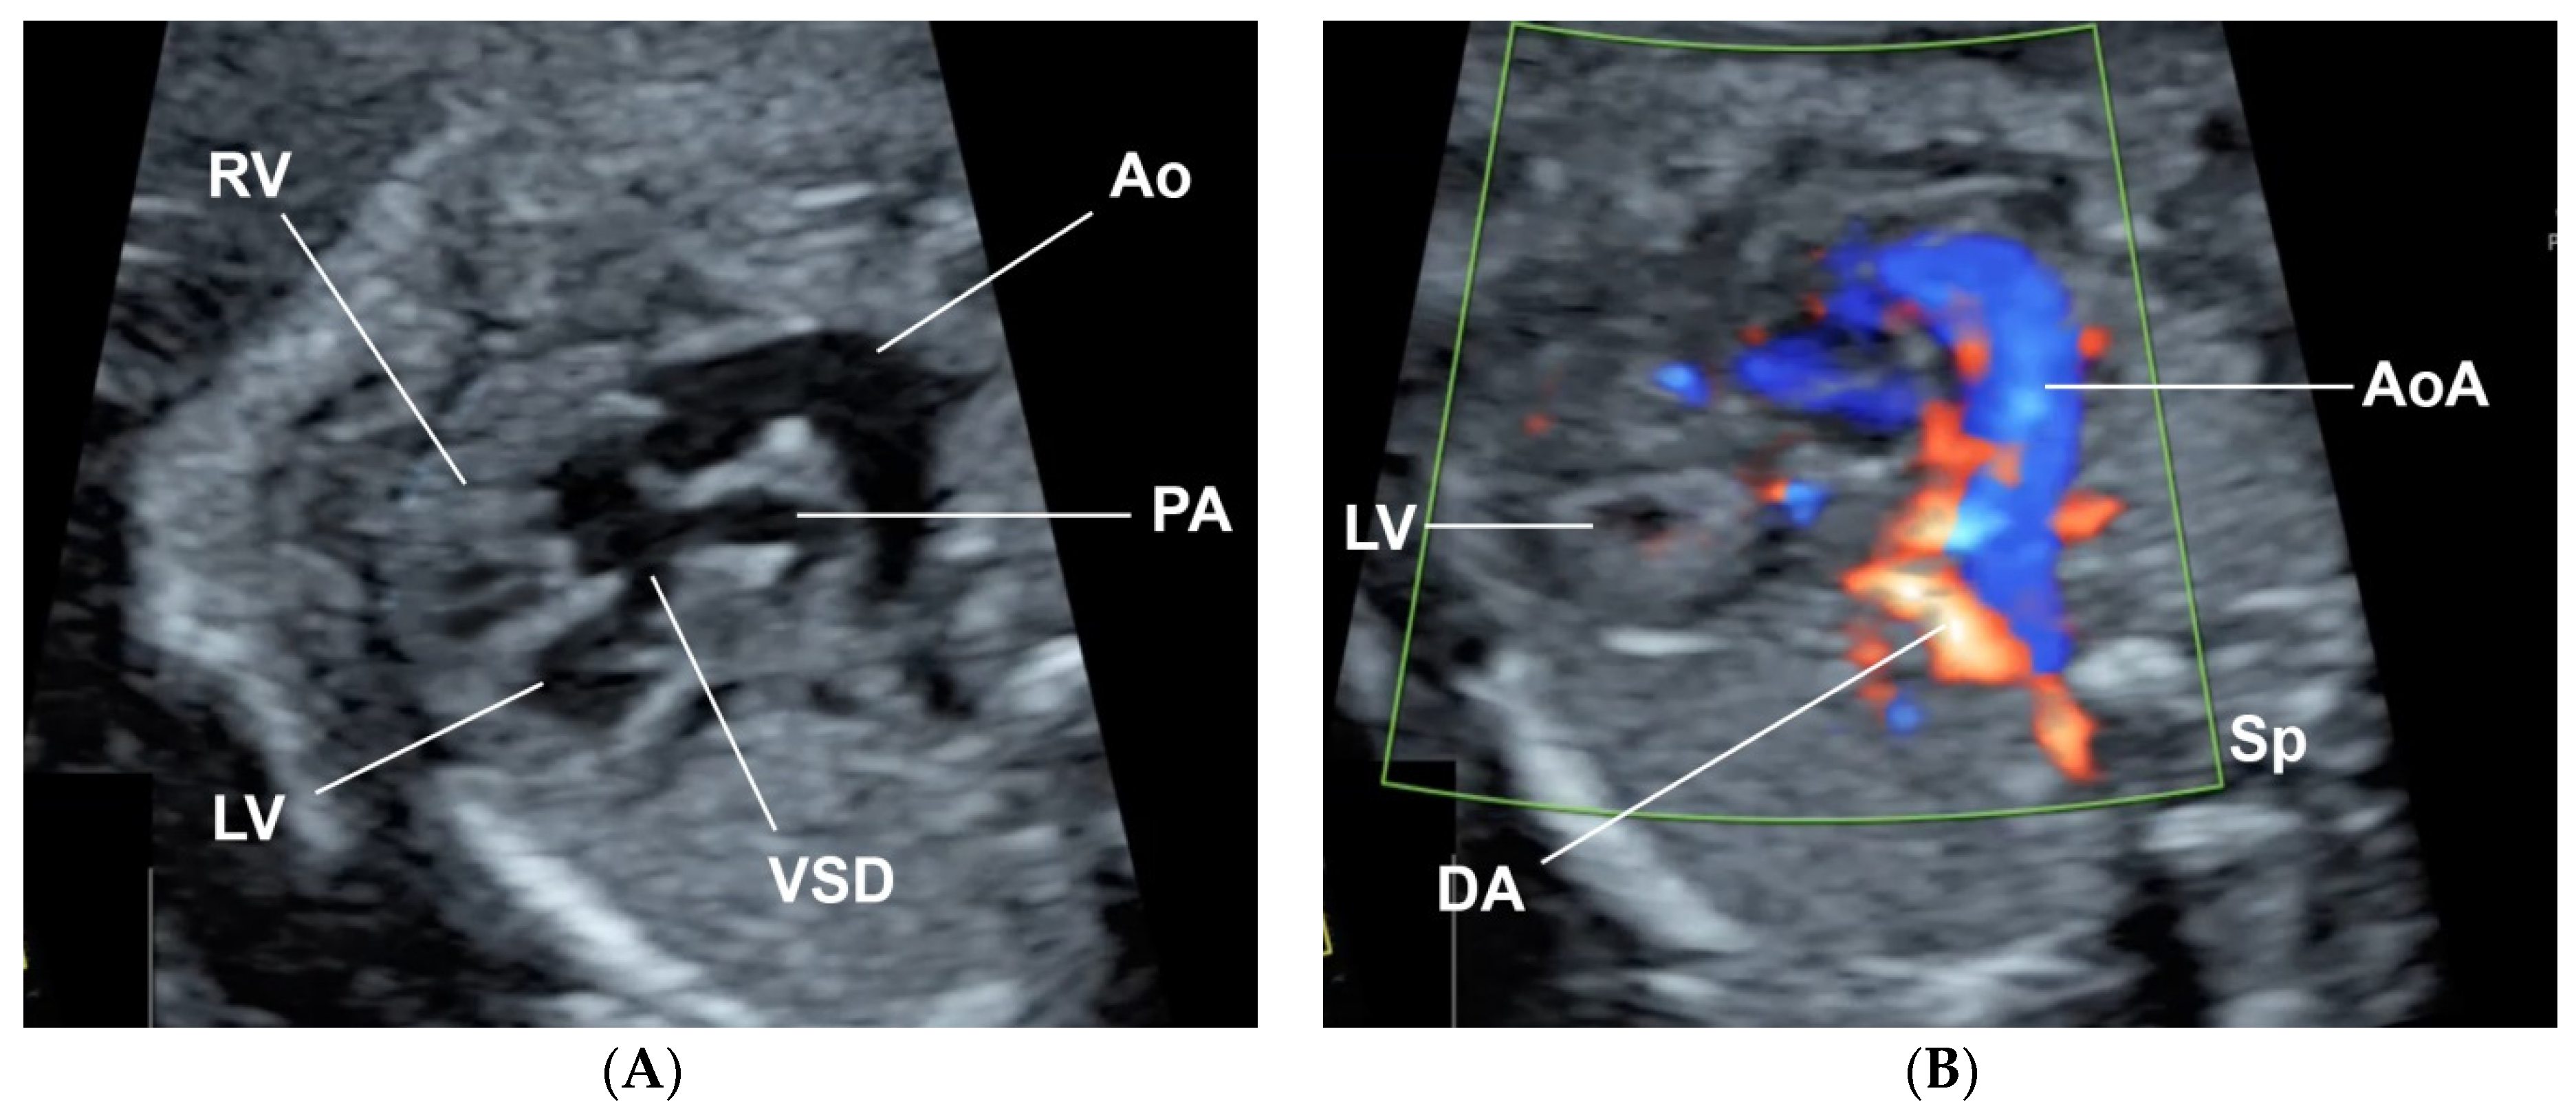

A 32-year-old pregnant woman, G4 P2102, attended her first visit of antenatal care at 23+3 weeks of gestation. Ultrasound examination for anomaly screening demonstrated cardiac defects, including double-outlet right ventricle: DORV-TOF type, with severe pulmonary stenosis (Figure 1) and left superior vena cava. Detailed ultrasound showed no associated abnormalities. Fetal biometry was consistent with gestational age except abdominal circumference and estimated fetal weight, which were relatively low (at 10th percentile), reflecting some degree of growth restriction. However, detailed ultrasound on the follow-up scans at 28 weeks of gestation showed subtle abnormalities, including malrotation of both kidneys, the hilum or renal pelvis facing posteriorly to the abdominal wall (Figure 2). Furthermore, 3D-ultrasound revealed abnormal external ear structure (markedly prominent crus of anti-helix) (Figure 3). Non-stress tests (NST) showed spontaneous fetal heart rate (FHR) accelerations (normal reactive tests) (23+3 weeks). Interestingly, the fetus showed persistent non-response to acoustic stimulation tests at 26, 30, 32, 36 and 38 weeks (no FHR accelerations as well as no quickening perceived by ultrasound) (Figure 4), probably reflective of auditory dysfunction. Based on the findings of heart defect, ear defect, renal defect and growth restriction, several differential diagnoses were listed, including CHARGE syndrome. Theoretically, fetal blood sampling for molecular genetic tests should be performed. Nevertheless, since no lethal condition was identified and the couple wanted to continue pregnancy regardless of investigation results, prenatal invasive diagnosis was avoided, and we waited for postnatal work-up instead. She had no significant underlying disease and no familial history of hereditary diseases. Her pregnancy was uneventful except that she developed gestational diabetes (GDM) at 28 weeks of gestation, which was well-controlled with diabetic diet.

Figure 1.

Double-outlet right ventricle (DORV): (A) TOF type, small pulmonary artery (PA) and (B) reverse flow in the ductus arteriosis (DA) (Ao: ascending aorta; AoA: aortic arch; LV: left ventricle; RV: right ventricle; Sp: spine; VSD: ventricular septal defect).